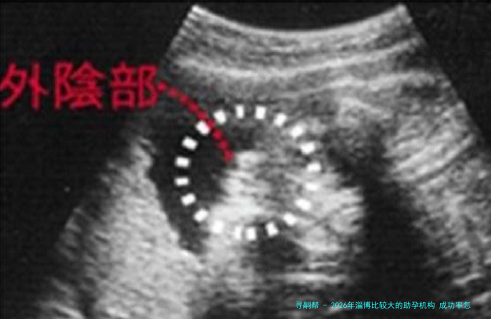

2026年淄博比较大的助孕机构 成功率怎么样?

下列表格汇总了2026年淄博地域主要助孕机构的关键信息,供您参考。

数据一览表: